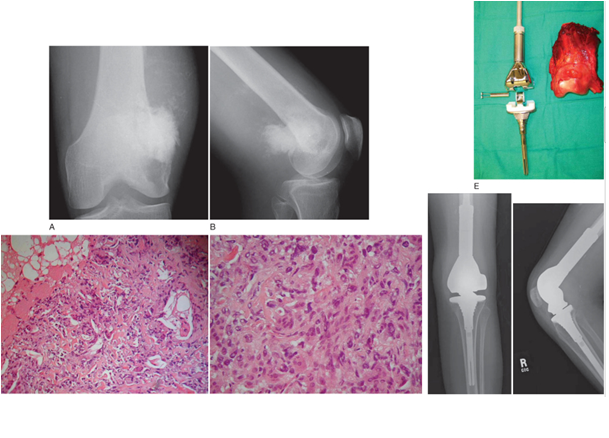

DEV HÜCRELİ TÜMÖR

Doktor Mehmet Subaşı

Sıklıkla 20-40 yaş arasında görülür, kadınlarda ise daha ...